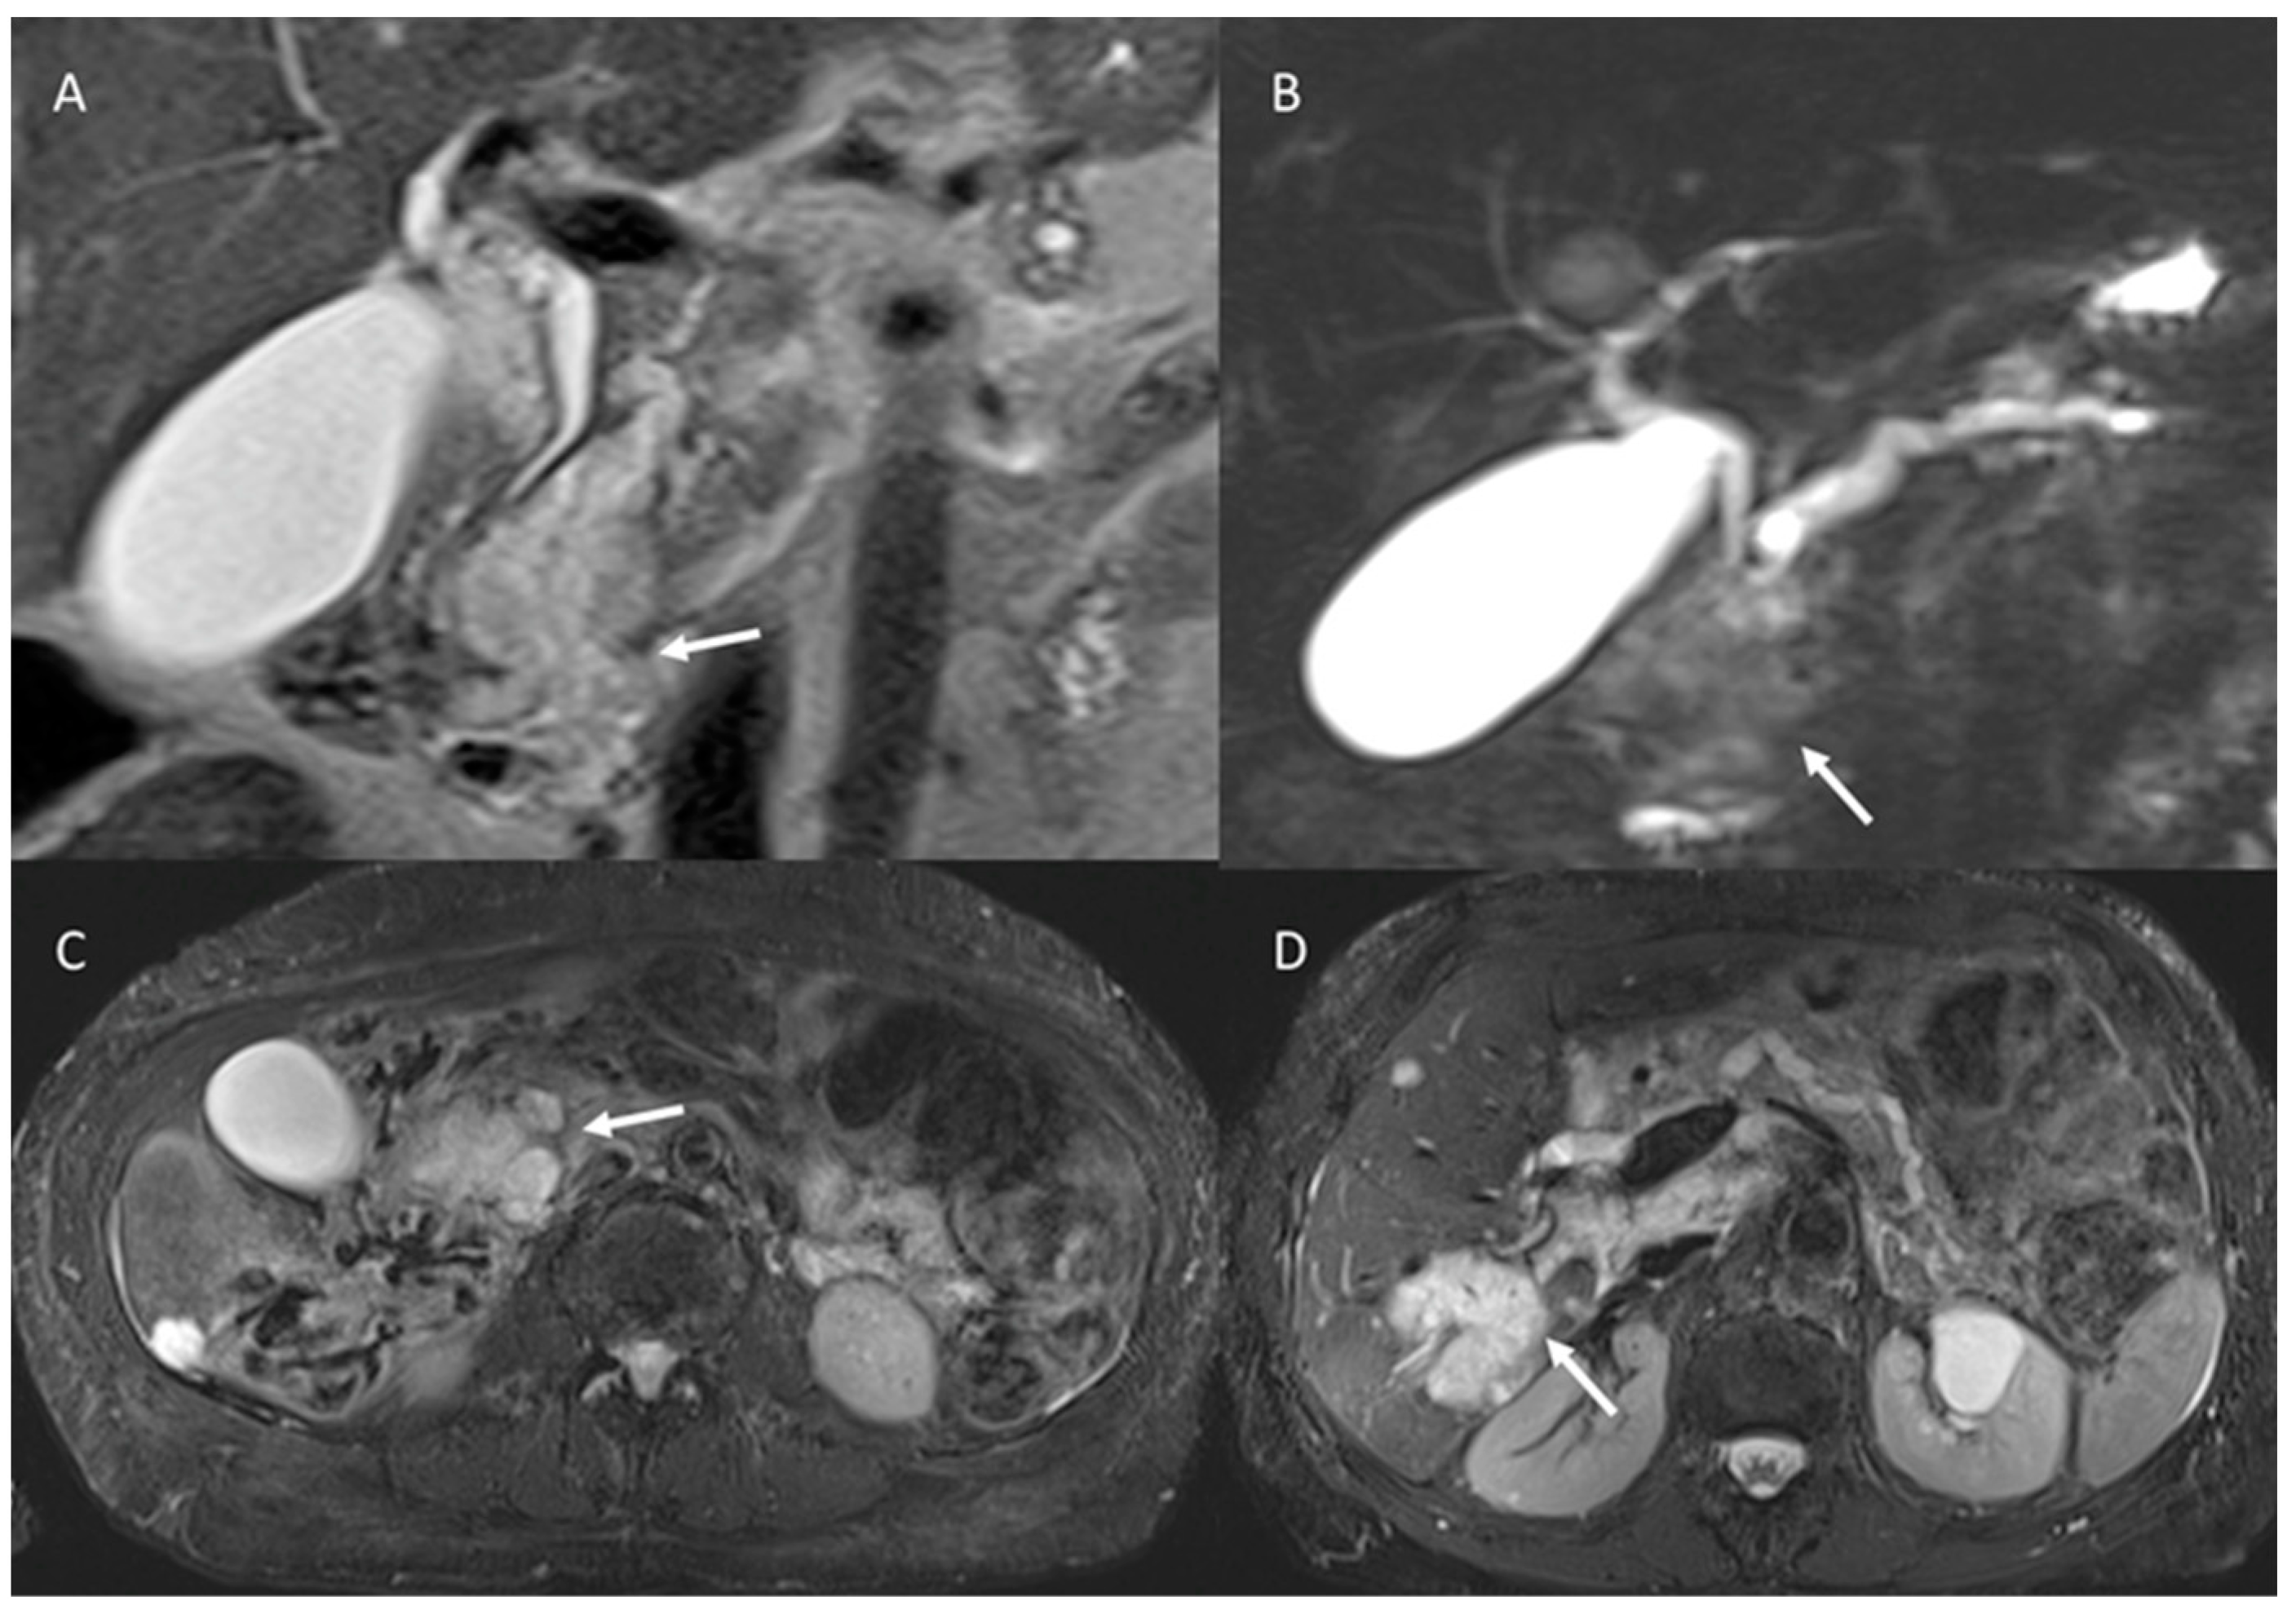

- Granata, V.; Grassi, R.; Fusco, R.; Galdiero, R.; Setola, S.V.; Palaia, R.; Belli, A.; Silvestro, L.; Cozzi, D.; Brunese, L.; et al. Pancreatic cancer detection and characterization: State of the art and radiomics. Eur. Rev. Med. Pharmacol. Sci. 2021, 25, 3684–3699. [Google Scholar] [CrossRef] [PubMed]